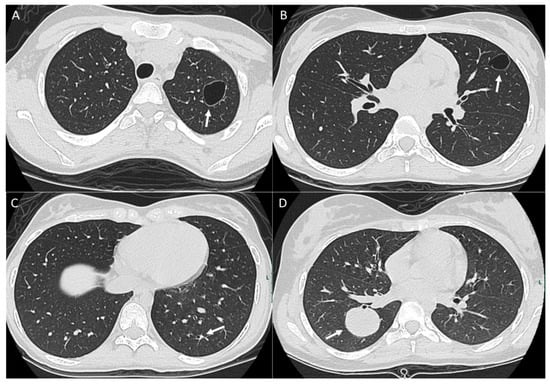

2.1. Parenchymal Metastasis

2.2. Vascular Metastasis

3. Pleura